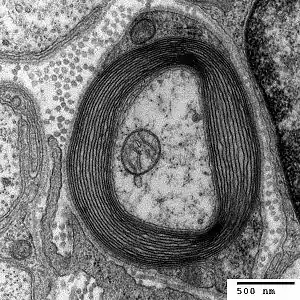

| Nerve with myelin sheath | |

HNPP is caused by a mutation in the gene PMP22, which makes peripheral myelin protein 22. This protein has a role in the maintenance of the myelin sheath that insulates nerves, resulting in insufficient conductivity in the nerves. HNPP is part of the group of hereditary motor and sensory neuropathy (HMSN) disorders and is linked to Charcot–Marie–Tooth disease (CMT).[5]

The condition is caused by a mutation in one copy of the gene PMP22 (peripheral myelin protein 22, located at locus 17p11.2). This makes it autosomal dominant.[8] PMP22 is involved in maintaining the myelin sheath that surrounds nerves to facilitate conductivity.[5] The mutation causes haploinsufficiency, where the activity of the normal gene is insufficient to compensate for the loss of function of the other gene.[9]

The peripheral myelin protein 22 gene encodes a 22-kD protein that comprises 2 to 5% of peripheral nervous system myelin.[10]